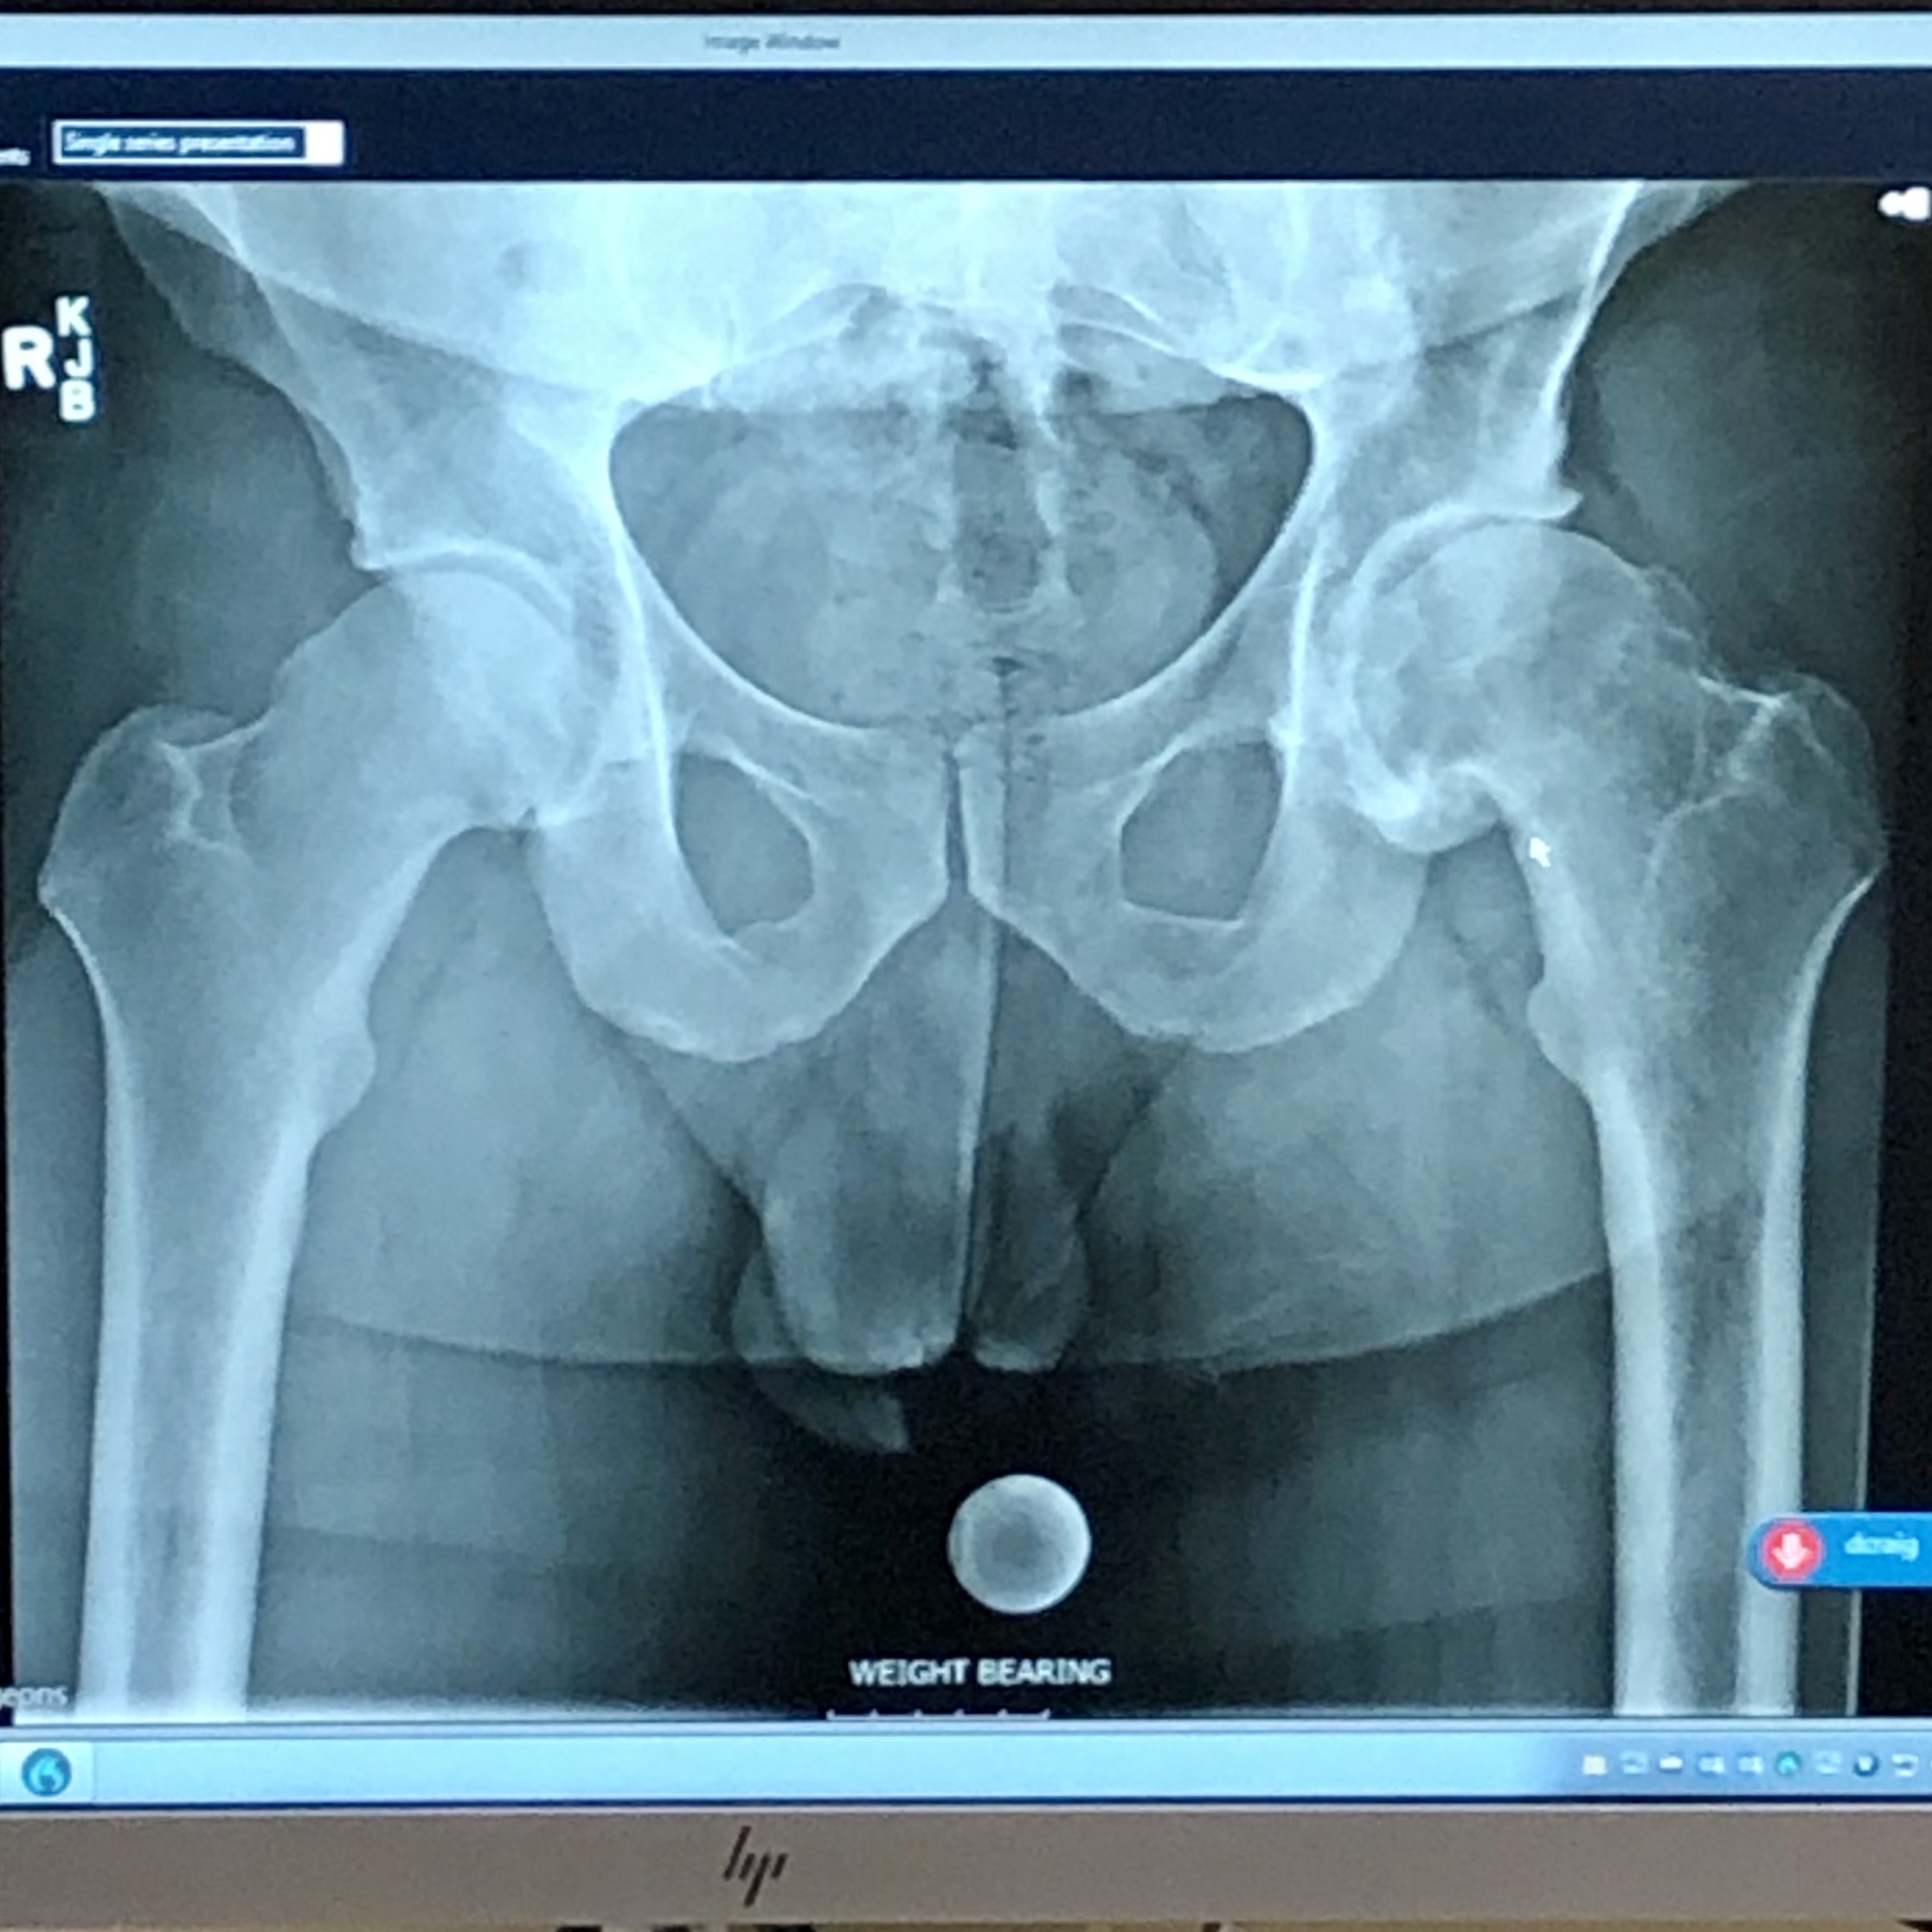

For anyone who hasn’t read this post for a week, here is a little perspective for everyone on the degeneration in my left hip. This first x Ray was taken 6/6/11 when I was 31 years old, still in the prime of my competition days. The second x Ray is from a week ago when my Ortho informed me I had the worst case of Osteo arthritis he’s ever seen in a 39 year old (8 years folks)… it’s amazing how fast things can change, and one of the biggest changes here, is not only the lack of soft tissue between the head of my left femur and the acetabellum, but also the head of my left femur itself… kinda crazy

Wow now I can really see the difference. I noticed that your hip had the white ring with the other image it really shows.

It actually looks like your whole pelvis is crooked? Is it?

I believe that’s from the way the x Ray tech had me stand last Thursday. She shifted all my weight to the left and made me stand in the most excruciatingly painful and awkward position ever. I think it was to pronounce that left side even more